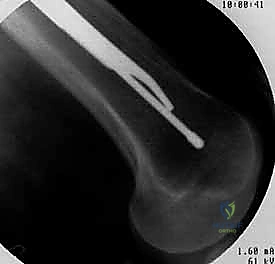

3. إحداث الشق الجراحي ونقطة الدخول

من خلال شق جراحي صغير جداً (حوالي 3 إلى 5 سم) أعلى الفخذ (فوق المدور الكبير)، يتم الوصول إلى قمة عظمة الفخذ. يتم إدخال سلك دليلي (Guide Wire) دقيق لتحديد نقطة الدخول المثالية للقناة النخاعية.

4. توسيع القناة وإدخال المسمار

يتم استخدام أدوات حفر خاصة (Reamers) لتوسيع القناة النخاعية بلطف لتستوعب المسمار المصنوع من التيتانيوم. بعد ذلك، يتم انزلاق المسمار النخاعي الرئيسي داخل العظم حتى يصل إلى العمق المطلوب.